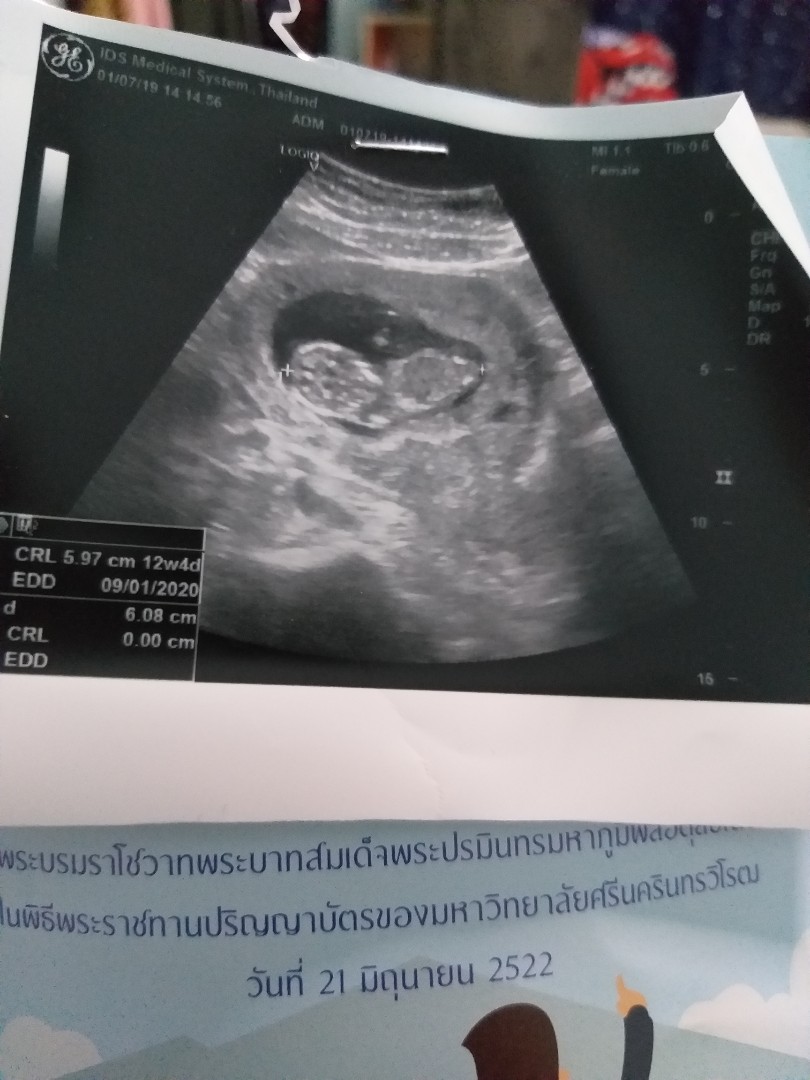

ญ จร้า

ผู้หญิง